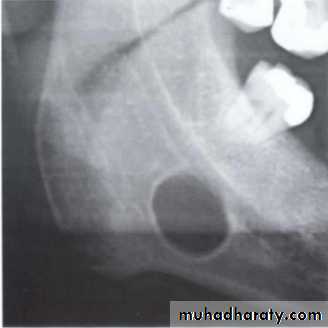

Benign cyst: lack of peripheral cortex(retention

pseudo cyst) indicates that it originated in the

sinus (non-odontogenic origin).

principles of radiographic interpretation